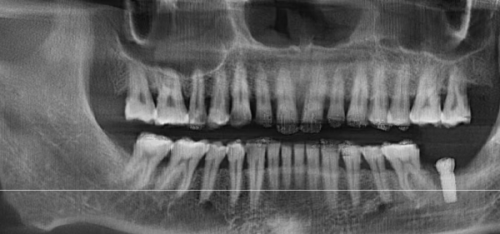

虽然种植牙不能用医疗保险报销,但了解其费用构成和影响因素,能让患者更好地规划自己的支出。种植牙的费用主要包括种植体的费用、基台的费用、牙冠的费用以及手术费用和检查费用等。种植体的品牌和材质是影响费用的重要因素,不同的品牌和材质价格差异较大。例如,进口的高端种植体价格可能会比国产的种植体高出特别多。牙冠的材料也有多种选择,如烤瓷牙冠、全瓷牙冠等,全瓷牙冠相对来说价格会更贵一些。此外,患者的口腔状况也会影响费用,如果患者口腔存在炎症、骨量不足等问题,可能需要精良行相应的治疗,这也会增加整体的费用。